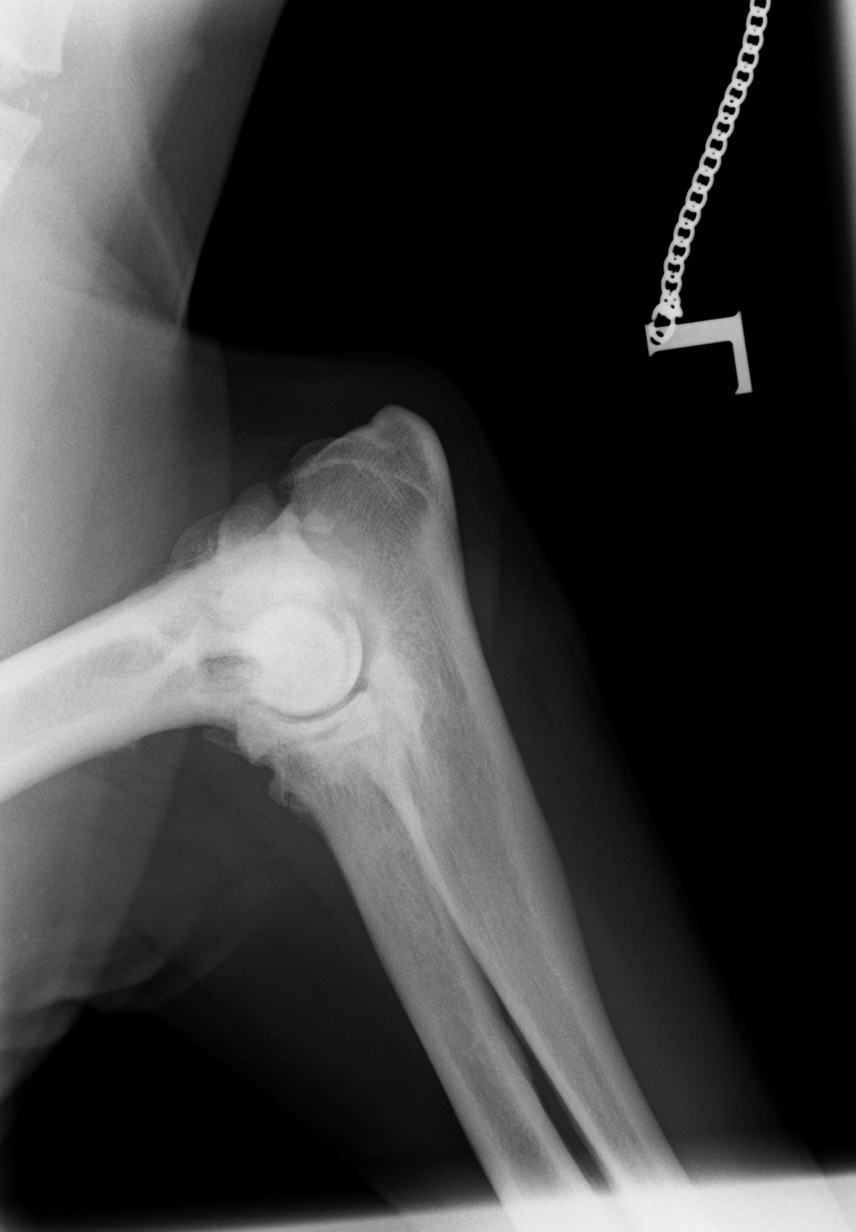

Im August 2013 wurde ein acht Jahre alter männlich kastrierter Labrador mit beidseitig hochgradiger  Ellenbogengelenksarthrose vorgestellt. Der Hund war beidseits wegen eines frakturierten Processus Coronoideus (Der Proccesus Coronoideus stellt einen wichtigen knöchernen Stabilisator des Ellenbogengelenks dar) operiert, einseitig nachoperiert und auf beiden Seiten mehrfach mit Cortison-Injektionen behandelt worden.

Noch im August 2013 wurde er in Vollnarkose beidseits mit der Thrombozytentherapie behandelt. Thrombozyten sind sogenannte Blutplättchen, die eine wichtige Rolle bei der Blutstillung spielen. Sie heften sich bei Verletzungen an das umliegende Gewebe an und sorgen dafür, dass u.a. geschädigtes Gewebe wieder "aktiviert" werden kann. Bei dieser Behandlungsmethode werden diese aus dem eigenen Blut des Hundes gewonnen und aufkonzentriert. Die Filtration mit V-Pet ist die Methode, um besonders viele und wirksame Thrombozyten schonend zu erhalten. Das Konzentrat wird anschließend in das geschädigte Gewebe gespritzt - in diesen Fall in das befallene Ellenbogengelenk des Labradors.